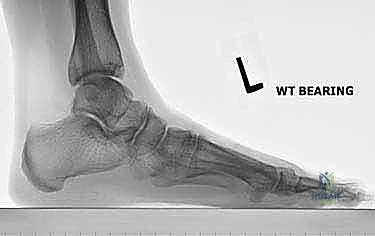

- الأشعة السينية أثناء الوقوف (Weight-bearing X-rays): وهي أهم أداة تشخيصية. الأشعة العادية والسرير فارغ لا تظهر المشكلة الحقيقية؛ يجب التقاط الأشعة والمريض يقف ليتحمل وزن الجسم، مما يظهر الانهيار الفعلي للمفاصل وتضيق المسافات بين العظام.